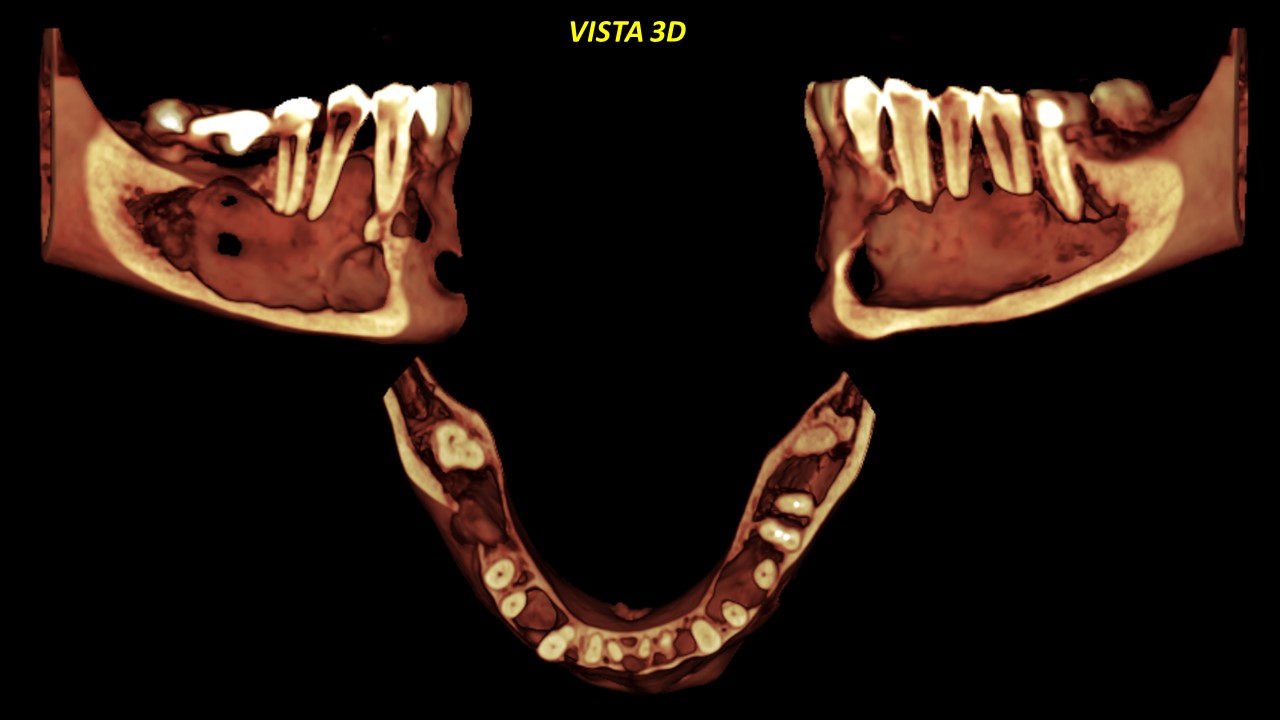

Figura 8

Figura 9

Signos tomográficos a descartar probable recurrencia de lesión quística (Queratoquiste Odontogènico). Esta entidad también puede ser observada de manera clara en las diferentes reconstrucciones tridimensionales resaltando sus características. (Figuras 8 y 9).